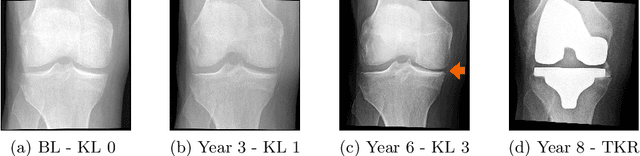

A vast majority of deep learning methods are built to automate diagnostic tasks. However, in clinical practice, a more advanced question is how to predict the course of a disease. Current methods for this problem are complicated, and often require domain knowledge, making them difficult for practitioners to use. In this paper, we formulate the prognosis prediction task as a one-to-many sequence prediction problem. Inspired by a clinical decision making process with two agents -- a radiologist and a general practitioner -- we propose a generic end-to-end transformer-based framework to estimate disease prognosis from images and auxiliary data. The effectiveness and validation of the developed method are shown on synthetic data, and in the task of predicting the development of structural osteoarthritic changes in knee joints.